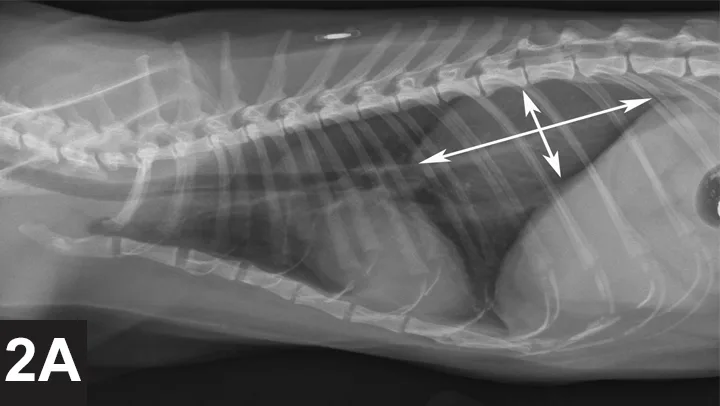

Lateral thoracic x-ray of a cat with arrows delineating soft-tissue opacity mass in the dorsocaudal field.

Thoracic radiographs (Figures 2A and 2B) were obtained to check for primary or metastatic neoplasia; an approximately 8.3 cm long, 3.8 cm tall, and 3.6 cm wide soft-tissue mass was present in the dorsal aspect of the right caudal thorax (white arrows), occupying the majority of the right caudal lung lobe. The aortic arch is prominent in the ventrodorsal view (black *); this is common in geriatric felines and may be a variation of normal or possibly an indication of systemic hypertension. The finding of a mass in the lung of this cat supports a diagnosis of a primary pulmonary carcinoma originating from the right caudal lung lobe with metastasis to the third digit of the right pelvic limb. This syndrome is described in several case reports.1-3 Most cats have swelling of one or more digits with radiographic evidence of osteolysis of the affected digit(s). The tendency of feline pulmonary carcinomas to metastasize to one or more digits is not understood, and no specific treatment has been rewarding.

FIGURE 2A

VD thoracic x-ray of cat with symbols marking aortic arch and soft-tissue opacity mass in the caudal right field.

FIGURE 2B